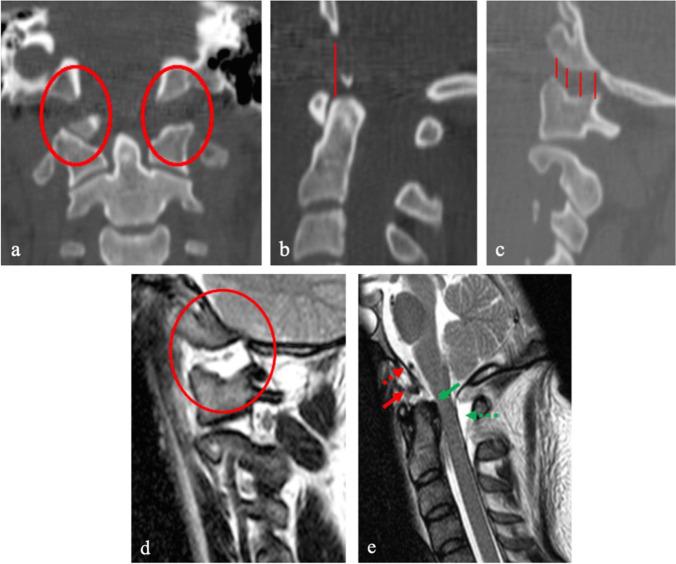

The cranio-vertebral junction (CVJ) was formerly considered a surgical "no man's land" due to its complex anatomical and biomechanical features. Surgical approaches and hardware instrumentation have had to be tailored in order to achieve successful outcomes. Nowadays, thanks to the ongoing development of new technologies and surgical techniques, CVJ surgery has come to be widely performed in many spine centers. Accordingly, there is a drive to explore novel solutions and technological nuances that make CVJ surgery safer, faster, and more precise. Improved outcome in CVJ surgery has been achieved thanks to increased safety allowing for reduction in complication rates. The Authors present the latest technological advancements in CVJ surgery in terms of imaging, biomaterials, navigation, robotics, customized implants, 3D-printed technology, video-assisted approaches and neuromonitoring.

颅颈交界区(CVJ)由于其复杂的解剖学和生物力学特征,以前被认为是手术的“无人区”。为了取得成功的结果,手术入路和硬件器械必须进行定制。如今,由于新技术和手术技术的不断发展,许多脊柱中心都广泛开展了 CVJ 手术。因此,人们一直在探索新的解决方案和技术细节,以使 CVJ 手术更安全、更快、更精确。由于安全性的提高,并发症发生率降低,CVJ 手术的结果得到了改善。作者介绍了 CVJ 手术在影像学、生物材料、导航、机器人技术、定制植入物、3D 打印技术、视频辅助入路和神经监测方面的最新技术进展。